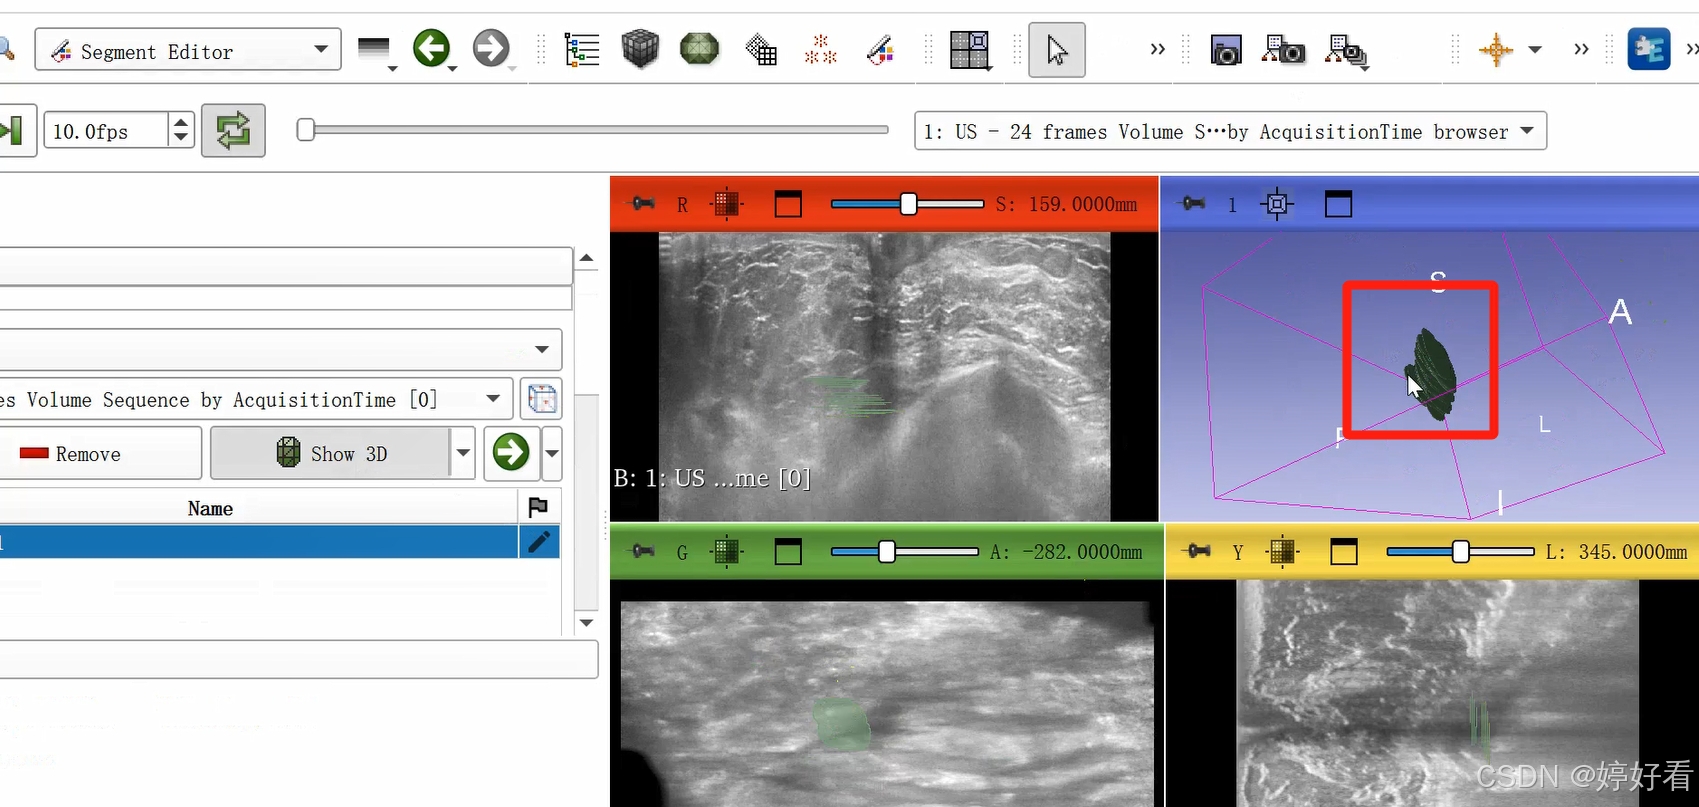

2.5 选中以下居中的符号,使绘制好的三维图像居中。

2.6 使用Fill between slices功能

上一步中完成的三维图像不是完整连续的三维图像,是一层一层的。Fill between slices这个功能可以自动填充每一层之间的间隙。选中Fill between slices,然后依次点击Initialize-Apply。